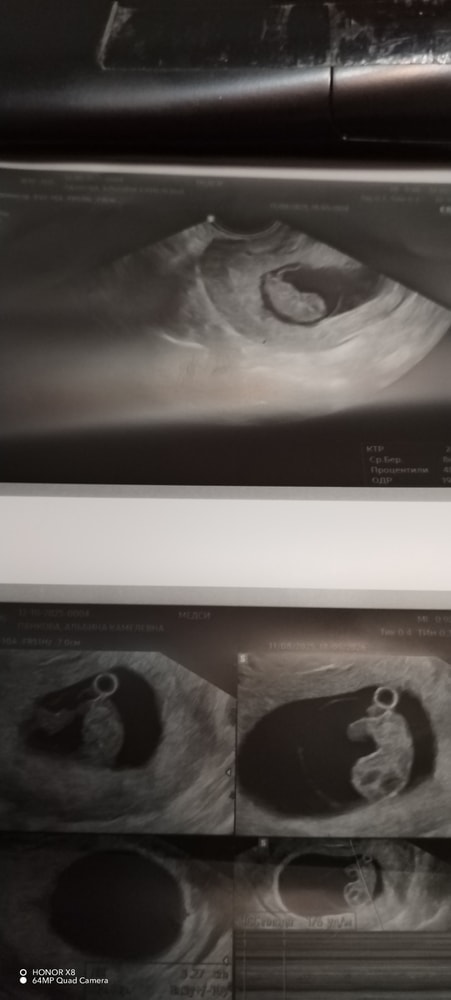

9 недель 🥰

Наши будни, наши неделькиНачалась сегодня девятая неделька. На учёт поставили в 7 недель. В 8 нед ушла на больничный. Токсикоз, который я ждала с 4х нед наступил в 8нед. С 6-7 нед токсикоз себя проявлял, тошнотой, меня мутило, я реагировала на вонючие запахи, не могла ничего толком покушать. С 8 недели меня начало с утра рвать. Вот это был аттракцион 😅😅😅. Спасалась цитрусовыми потому что их мне только и можно было кушать. Было сильное газообразование, раздувало, как жабу. Я постоянно сплю 😴😴😴полюбилось мне днём прилечь на часика 2 и кемарнуть. Эмоциональное состояние нормальное. Грудь самое любимое мне кажется на бб. Грудь перестала болеть, она живёт своей жизнью. Она большая, налитая, но болит только ночью, когда с боку на бок переварачиваешься. Потоотделение: я воняю, дезики не спасают, они делают ещё хуже. Подмышки текут. Это кошмар. Низ живота не тянет, потягивает то справа, то слева. До 8 недели жёлтое тело давало о себе знать. Сейчас тишина. Хожу на узи каждую неделю, мне так спокойнее. Воскресенье встречались с моей бусинкой. Уже большая, плавает, шевелится. В целом всё хорошо. Я готова на всё лишь бы с бусинкой всё было хорошо ❤️